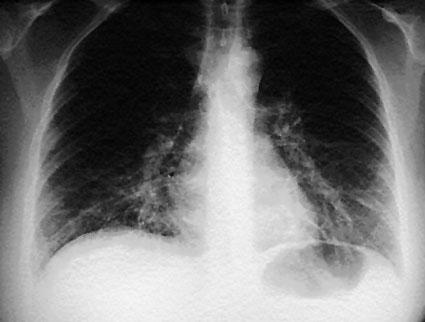

Рентгеновото изследване установява най-често сегментни или лобарни инфилтрати, което налага да се направи диференциална диагноза.